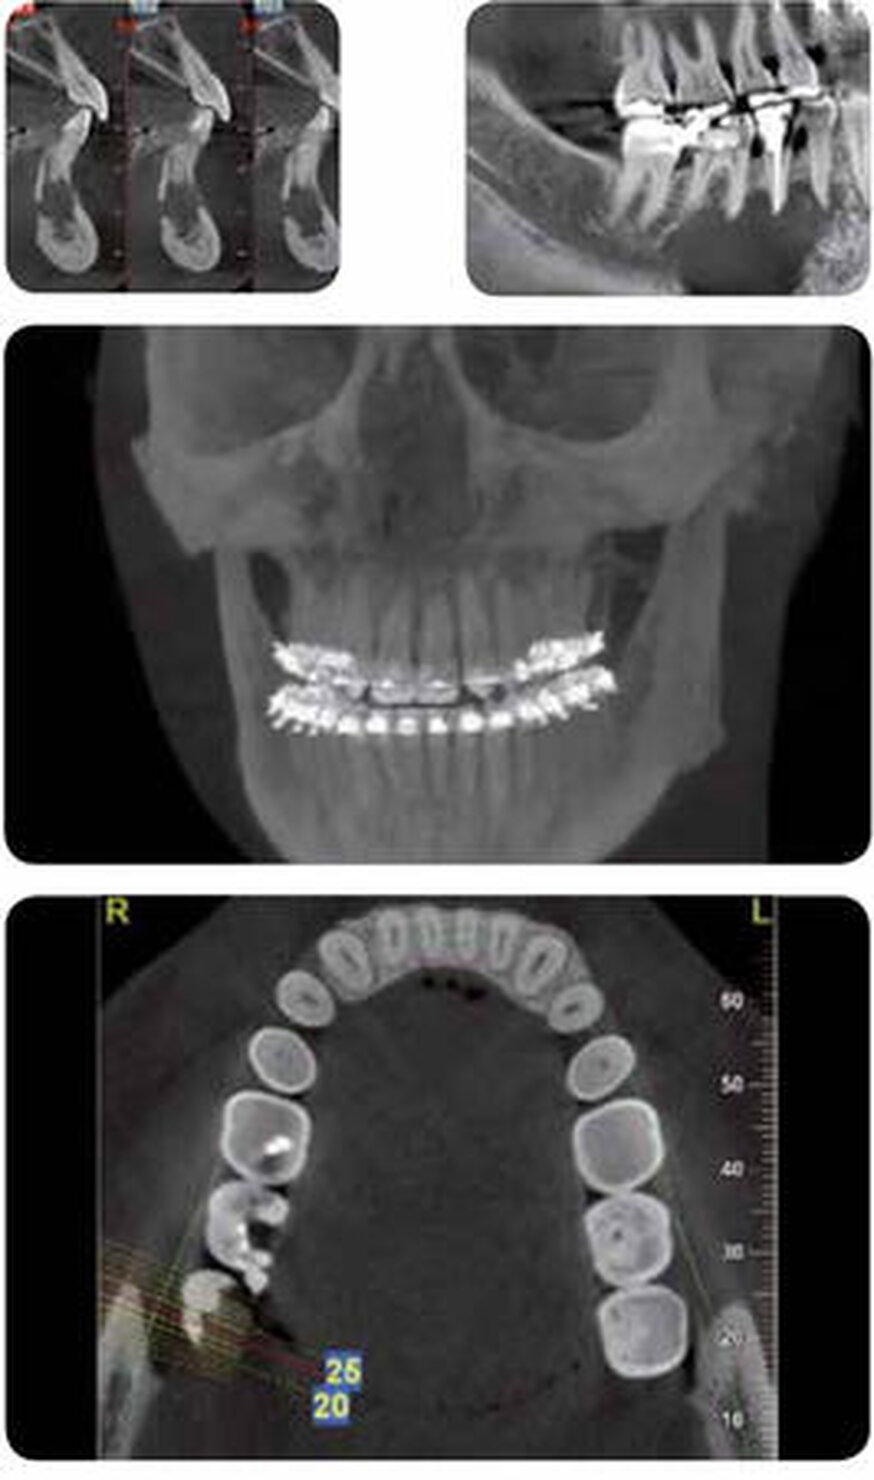

Implantologia

La tecnologia Cone Beam per la creazione di immagini 3D rappresenta uno strumento più efficace per la valutazione dei siti implantari. Le immagini ottenute da un volume 3D possono mostrare patologie potenziali e anomalie strutturali con una precisione senza precedenti.Queste immagini influenzano la scelta del tipo di impianto che dovrà essere utilizzato, del suo posizionamento e della sua larghezza, nonché le considerazioni sulla velocità del processo di osteointegrazione e possibili rigetti.

Chirurgia

Questa disciplina si occupa della correzione di diverse patologie dei tessuti duri e molli della zona maxillofacciale. Una scansione effettuata con i dispositivi NewTom mostra con esattezza caratteristiche come la presenza di denti o di fratture, la densità e l’altezza dell’osso, la forma e l’inclinazione della radice. Nel caso di scansioni post-operatorie,la presenza di elementi metallici non va a incidere sulla qualità dell’immagine. Al contrario, grazie alla bassa quantità di raggi necessaria, l’effetto scattering risulta quasi inesistente e le strutture anatomiche scansionate vengono visualizzate chiaramente.

Endodonzia-Periodonzia

Lo specialista che si occupa di endodonzia e periodonzia, per eseguire procedure come il trattamento di un dente fratturato, la terapia del canale mandibolare e la cura del tessuto adiacente al dente, necessita di immagini che gli permettano di identificare ogni particolare della zona trattata, determinare l’esatta patologia e pianificare accuratamente un trattamento efficace.